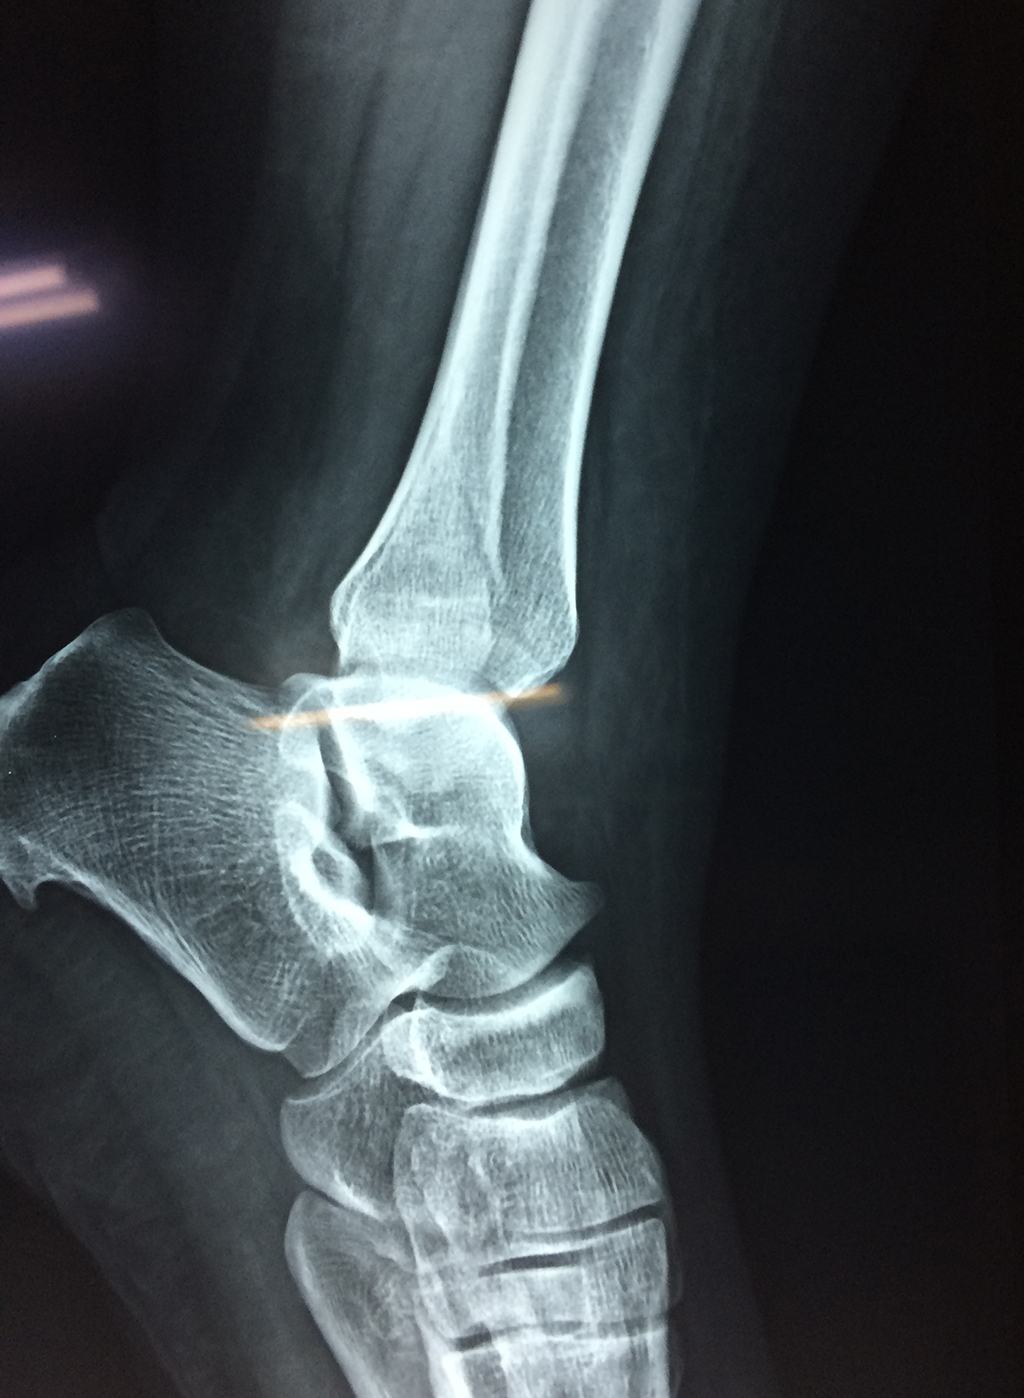

- Los extremos de los huesos están desalineados entre sí (desplazados).

- La fractura se extiende hasta la articulación del tobillo (fractura intra-articular).

- Los tendones o ligamentos (tejidos que sujetan los músculos y los huesos entre sí) están rotos.